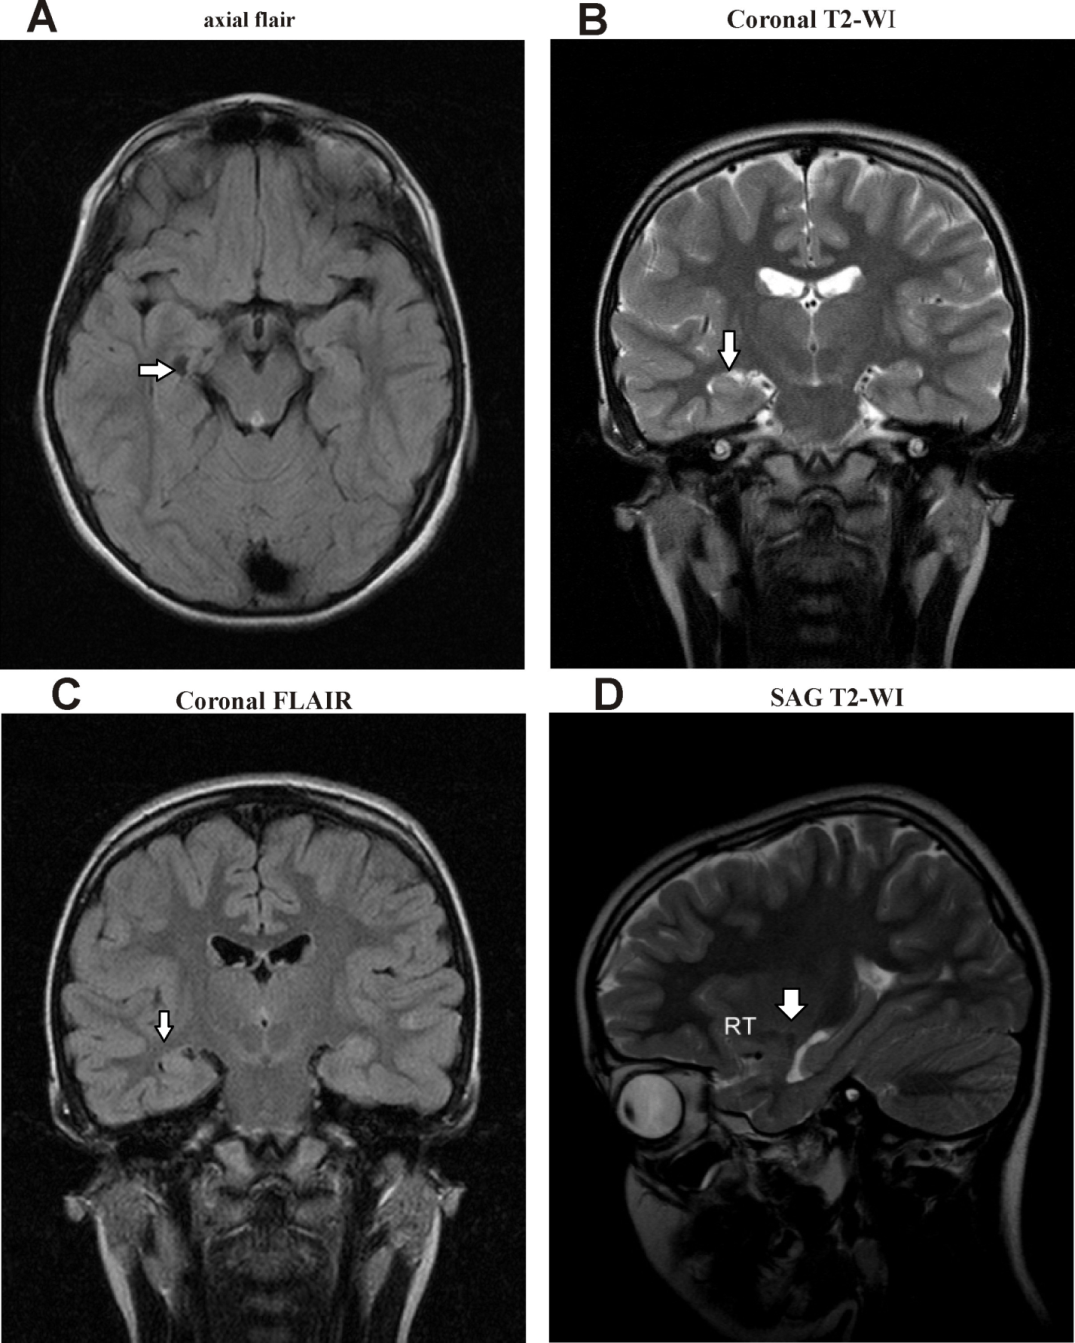

A) Hypersignal of the right hippocampus on coronal T2weighted MRI (a Coronal Mri Hippocampus With uhf magnetic resonance imaging (mri), the quantification of subtle differences in hippocampal strata, such as. Mri is the imaging modality of choice for evaluation of the hippocampus, and ct and nuclear medicine also improve the analysis. Magnetic resonance imaging is the preferred imaging technique for evaluating the hippocampus. (1) a memory impairment is usually the earliest and most. This. Coronal Mri Hippocampus.